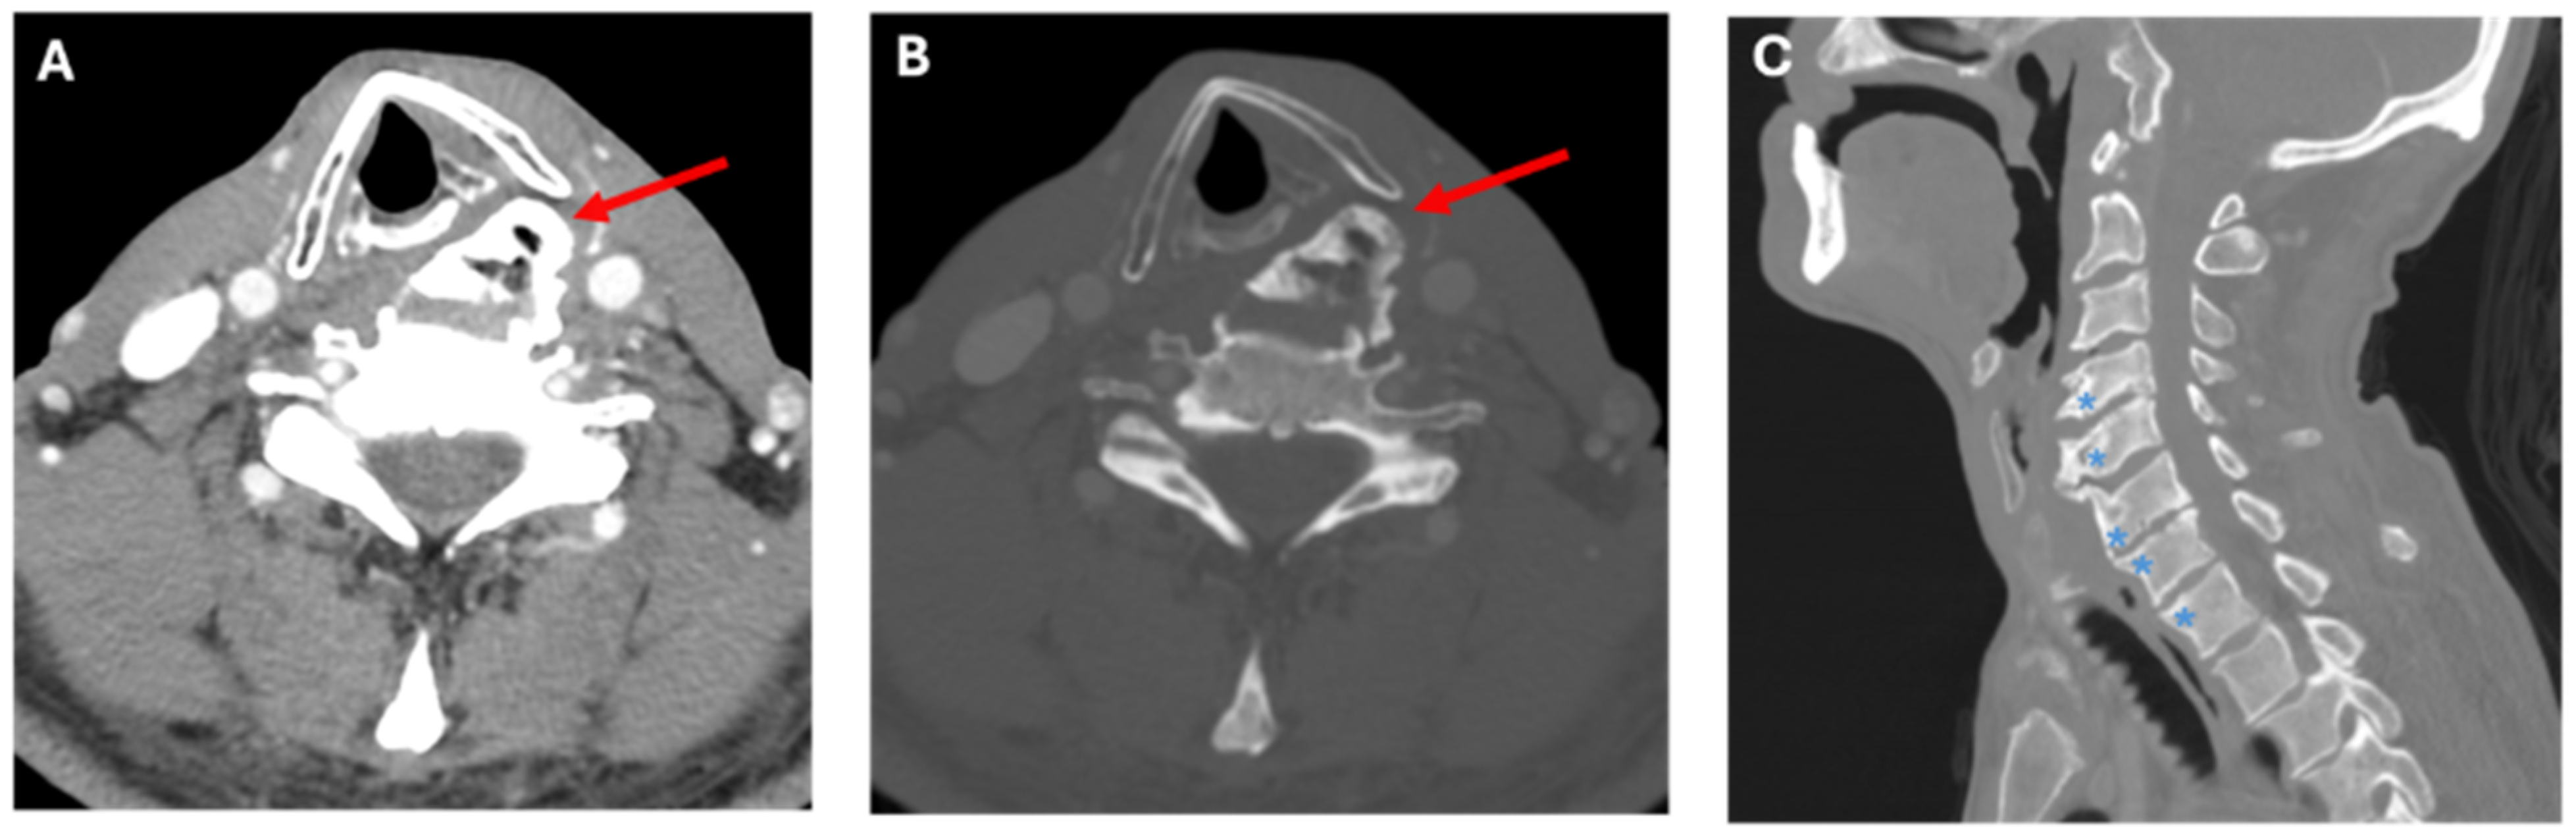

2.1. Case A